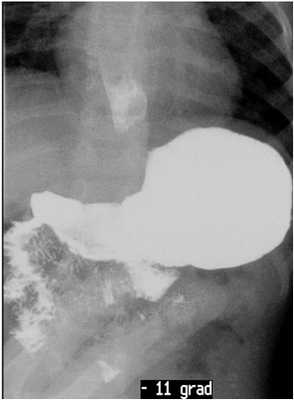

При отрицательных результатах пациент осматривается в положении Тренделенбурга (головной конец стола опускается вниз на 10-110, входит в «стандарт» диагностики в 1969 г., О.С. Радбиль).

Данный приём позволяет, увеличить процент выявляемости ГЭР и, особенно грыжи пищеводного отверстия диафрагмы [9], в частности, скользящую.

Далее стол переводится в положение параллельное полу.

Должна производиться нагрузочная проба: глотание густой контрастной массы [2] в объёме одного глотка (если пациент умеет осознанно глотать). В настоящее время приём не используется в виду отсутствия в Республике Беларусь возможности приобретения сульфата бария в виде порошка. Продвижение густого контрастного комка позволяет адекватно оценить эвакуационную способность пищевода, его моторику, особенности работы сфинктеров пищевода.

Следующий этап, при отрицательных результатах выше выполненных манипуляций, постановка водно-сифонной пробы.

Пациент укладывается на спину в положении на правом боку под углом 450 [2], указание на методику, предложенную Linsman в 1965 г.). Положительным считается проба, при которой происходит заброс содержимого желудка в пищевод. При этом можно осуществлять маятникообразные умеренные надавливания на переднюю брюшную стенку, для оценки состояния средне пищеводного сфинктера [3, 4, 5].